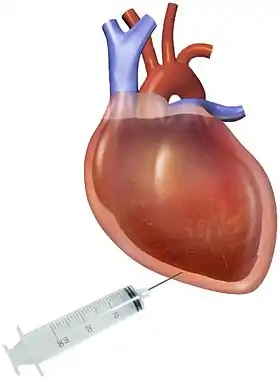

Pericardiocentesis: is a procedure in which fluid is aspirated from the pericardial cavity with a needle and catheter. This procedure can be used to analyze the fluid but more importantly can also provide symptomatic relief, especially in patients with hemodynamic compromise. Pericardiocentesis is usually guided by an echocardiogram to determine the exact location of the effusion and the optimal location of puncture site to minimize risk of complications.[5] After the procedure, the aspirated fluid is analyzed for gross appearance (color, consistency, bloody), cell count, and concentration of glucose, protein, and other cellular components (for example lactate dehydrogenase).[13] Fluid may be also sent for gram stain, acid fast stain, or culture if high suspicion of infectious cause.[1] Bloody fluids may also be evaluated for malignant cells.[13]

Pericardial effusion due to malignancy. Note bulbous heart and primary lung cancer in right upper lobe. Pericardiocentesis: fluid aspiration of hemorrhagic effusion

Pericardiocentesis: fluid aspiration of hemorrhagic effusion

Treatment depends on the underlying cause and the severity of the heart impairment.[1] For example, pericardial effusion from autoimmune etiologies may benefit from anti-inflammatory medications. Pericardial effusion due to a viral infection usually resolves within a few weeks without any treatment.[8] Small pericardial effusions without any symptoms don't require treatment and may be watched with serial ultrasounds.[2] If the effusion is compromising heart function and causing cardiac tamponade, it will need to be drained.[1] Fluid can be drained via needle pericardiocentesis as discussed above or surgical procedures, such as a pericardial window.[2] The intervention used depends on the cause of pericardial effusion and the clinical status of the patient.

Pericardiocentesis is the choice of treatment in unstable patients: it can be performed at the bedside and in a timely manner.[4] A drainage tube is often left in place for 24 hours or more for assessment of re-accumulation of fluid and also for continued drainage.[4] Patients with cardiac tamponade are also given IV fluids and/or vasopressors to increase systemic blood pressure and cardiac output.[1]

But in localized or malignant effusions, surgical drainage may be required instead. This is most often done by cutting through the pericardium and creating a pericardial window[1] This window provides a path for the fluid to be drained directly into the chest cavity, which prevents future development of cardiac tamponade. In localized effusions, it might be difficult to get safe access for pericardiocentesis, hence a surgical procedure is preferred. In case of malignant effusions, the high likelihood of recurrence of fluid accumulation is the main reason for a surgical procedure.[4] Pericardiocentesis is not preferred for chronic treatment options due to risk of infection.